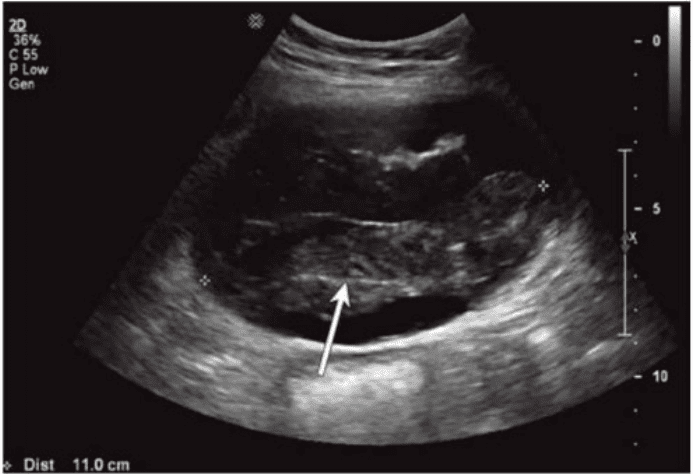

Which condition of the transplant kidney is indicated by the arrows on these images?